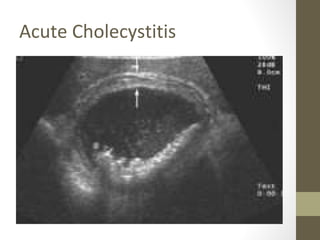

Rapid Case #13

• 46 yo female, G3P3

• Post Prandial Epigastric pain

• Exam: Obese, RUQ tender to palpation

• U/S: Multiple Gallstones with GB wall thickening

• DX: Acute Cholecystitis

Acute Cholecystitis

Rapid Case #13 •46 yo female, G3P3 • Post Prandial Epigastric pain • Exam: Obese, RUQ tender to palpation • U/S: Multiple Gallstones with GB wall thickening • DX: Acute Cholecystitis